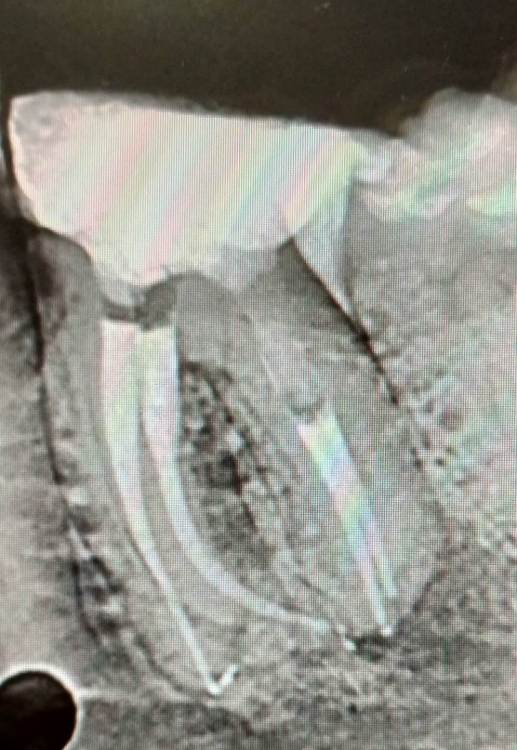

Ico Опубликовано 29 апреля, 2022 Автор Поделиться Опубликовано 29 апреля, 2022 Необратимый пульпит 47,я редко такой изгиб язычного видел. Префлеринг S1-S2(21 мм),скаут 8-10,патфаилы. Нитифлекс на 25к финиш 25.04 профаил.Мартенсита на то время не было.Паковка волна с эйчем. 5 Ссылка на комментарий